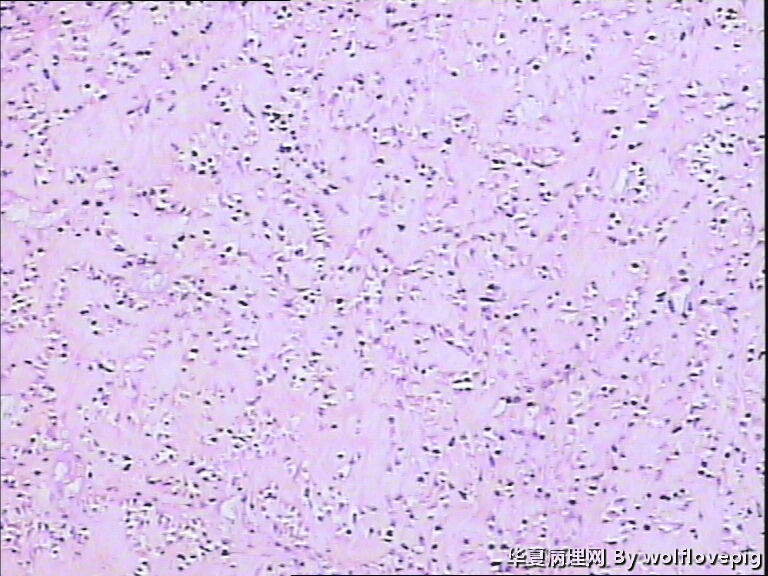

求助!肌瘤变性?

• 求助!肌瘤变性?图1

图1

平滑肌瘤伴间质玻璃样变性,像是冰冻的片子吧?》

上皮样平滑肌瘤,鉴别PECOMA

像平滑肌瘤玻璃变性

平滑肌瘤

上皮样平滑肌瘤

符合平滑肌瘤伴梗死,多取材寻找有无质软,肉质样变区,破碎的组织最麻烦,要慎重。